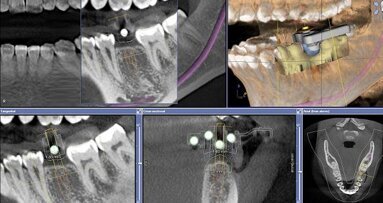

Following a discussion of the options for replacement of LR6, the patient elected for an implant-retained solution. A MegaGen AnyRidge 4 x 10 mm implant was placed utilising a surgical guide for position of the pilot hole. An immediate temporary crown was fabricated using the MegaGen fuse abutment and DMG Luxatemp. A silicone index of the diagnostic wax-up was fabricated and the temporary crown was polished and taken out of occlusion while the implant fully integrated (Fig. 3).

Following digital intraoral scanning (DIOS) of the opposing arch, working arch and buccal bite, a digital design was created using the biogeneric individual design mode. In this design mode on the CEREC Omnicam, the software evaluates the other teeth captured in the DIOS and tries to recreate what it believes to be the closest match to the original missing tooth (Figs. 9–11).